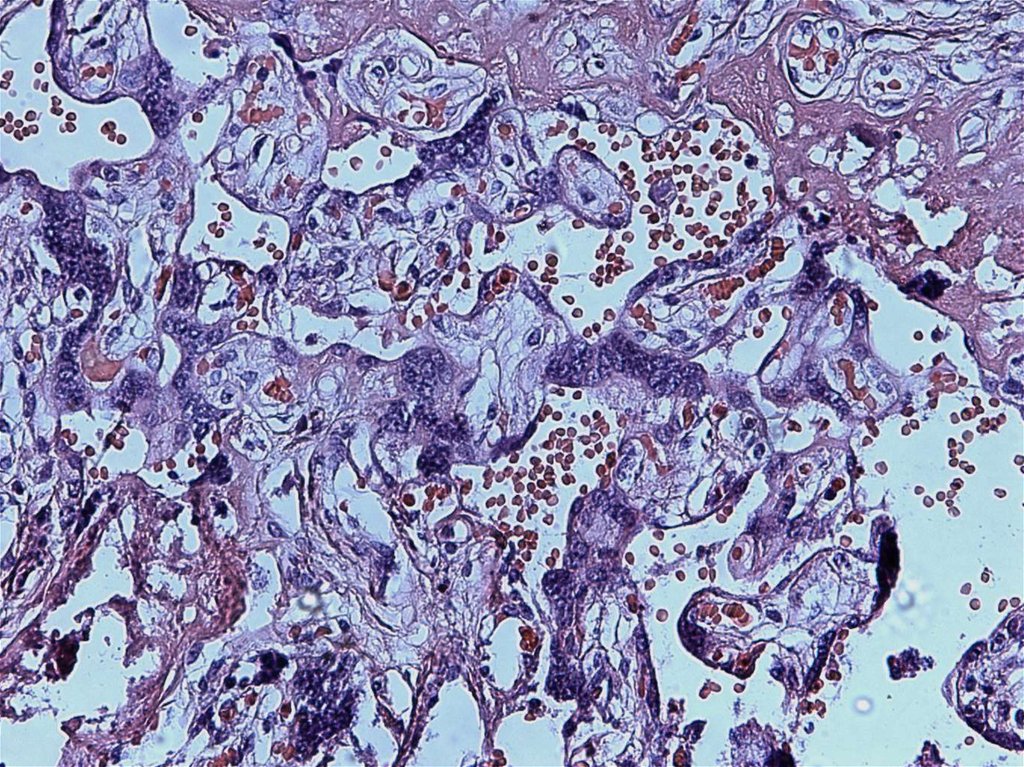

4. Плацентарная недостаточность:

болезни матери

гипоксические и трофические нарушения развития плода

гестационная последовательность (первичная, вторичная)

давность существования( хроническая,острая)

степень выраженности компенсаторноприспособительных реакций (декомпенсированная,

субкомпенсированная и компенсированная)